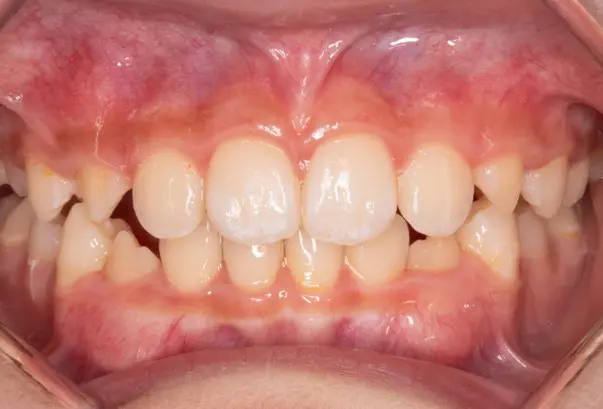

Crowding

Before